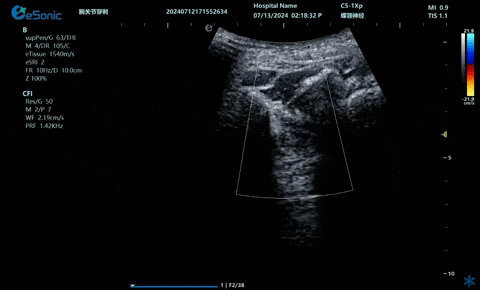

超声引导下蝶颚神经节阻滞术

大雁征-上颌动脉切面

疼痛康复领域中的肌骨超声应用,旨在实现对肌肉、肌腱、韧带、关节、神经、血管、筋膜、滑膜、滑囊、骨膜等组织结构的精确诊断评估。由于超声高频探头对上述机体组织的细微结构具有优异的分辨率,因此能够更为明确地评估这些组织的损伤和炎症状态。同时,超声设备的实时动态评估能力,使得对运动中的相关疾患也能进行准确的评估,这是其他诊断设备所不具备的优势。在康复治疗过程中,肌骨超声还用于介入穿刺治疗,如外周神经阻滞(PNB)、小关节注射、肌筋膜松解术、封闭、小针刀、冲击波治疗等。在超声引导下,这些治疗操作实现了可视化,从而真正意义上实现了精准医疗。以PNB为例,作为一种局部用药方式,其对患者全身干扰小,药物副作用少,且费用较低,因此仍然是临床治疗疼痛的主要方式之一近年来,超声技术在临床康复领域的应用日益凸显其优势。相较于传统的盲穿技术,超声引导下的PNB能够直观显示穿刺和注药过程,无需患者表达异感,避免了反复穿刺给患者带来的痛苦。这种技术显著提高了外周神经阻滞、静脉穿刺的成功率、精确性和安全性,同时减少了不良反应和并发症的发生,为患者带来了福音也相信在不久的将来,eHertz系列产品将会在全球医疗市场上掀起一场技术革新的风暴,让更多的人受益于我国医疗技术的进步。